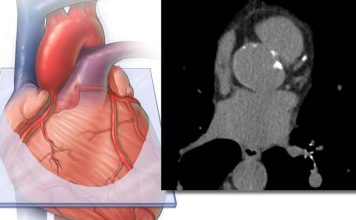

Investigadores de Mayo Clinic han desarrollado una nueva forma de predecir si los medicamentos existentes podrían readaptarse para tratar la insuficiencia cardíaca, uno de...